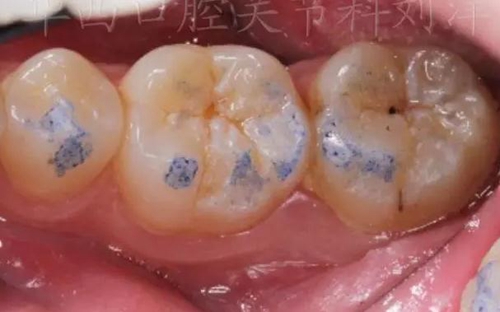

①先用100微米做粗調

▲ 圖1:100µm咬合紙

▲ 圖2:100µm咬合紙的效果